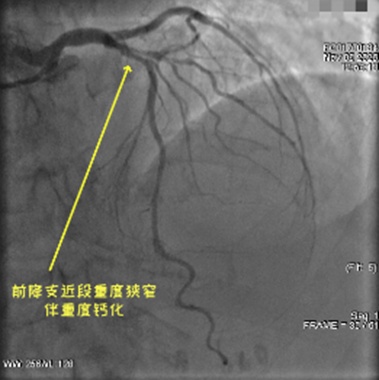

冠状动脉造影显示,卫阿姨的左前降支血管近段不仅狭窄加重,还伴有重度钙化。很多人不知道,冠状动脉钙化就像血管壁上结了一层“硬壳”,常规的介入手术中,球囊根本无法将其撑开,强行操作还可能导致血管撕裂、穿孔等致命风险,是心内科医生公认的“硬骨头”。

上海九院心内科卓杨教授——这位在冠心病介入领域经验丰富的专家,曾多次指导心内科开展复杂高危高难度的冠状动脉介入手术,建议采用冠状动脉内碎石术(IVL),这是一种处理冠状动脉严重钙化病变前沿的治疗方案。

这种技术的原理很巧妙:将特殊的冲击波球囊送到病灶处,通过释放低频冲击波,像“温柔的锤子”一样,在不损伤血管内膜的前提下,把坚硬的钙化斑块击碎。打个比方,就像给水管里的水垢“松绑”,既清除障碍,又不破坏管道本身。